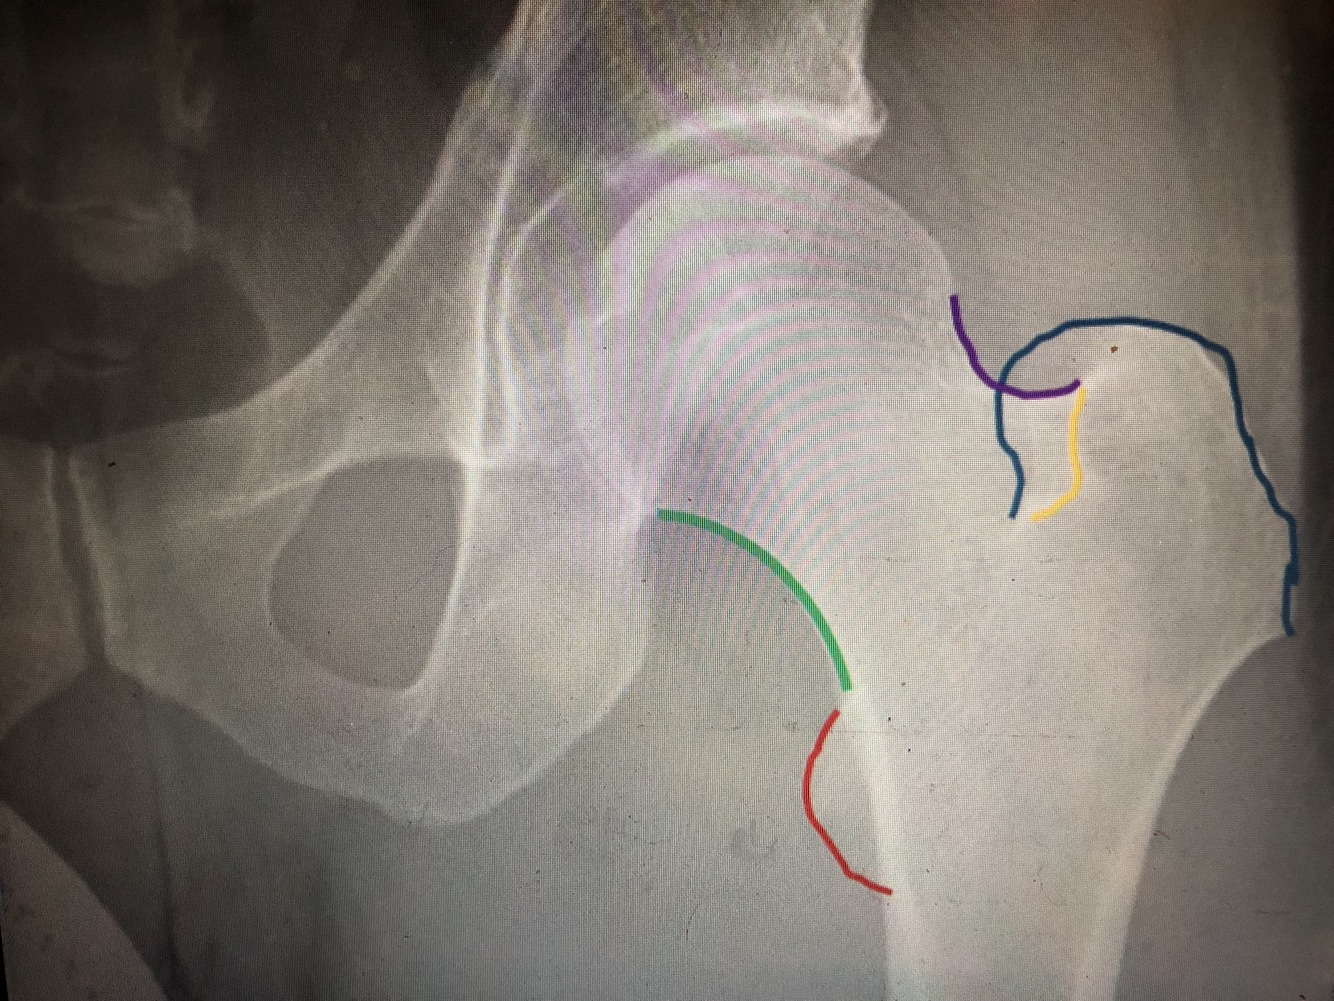

What is the green line?

Medial margin of femoral neck

What is the purple line?

Lateral margin of femoral neck

What is the red line?

Lesser trochanter

What is the blue line?

Greater trochanter

What is the yellow line?

Floor of trochanteric fossa (looks like part of intertrochanteric crest, but is not)